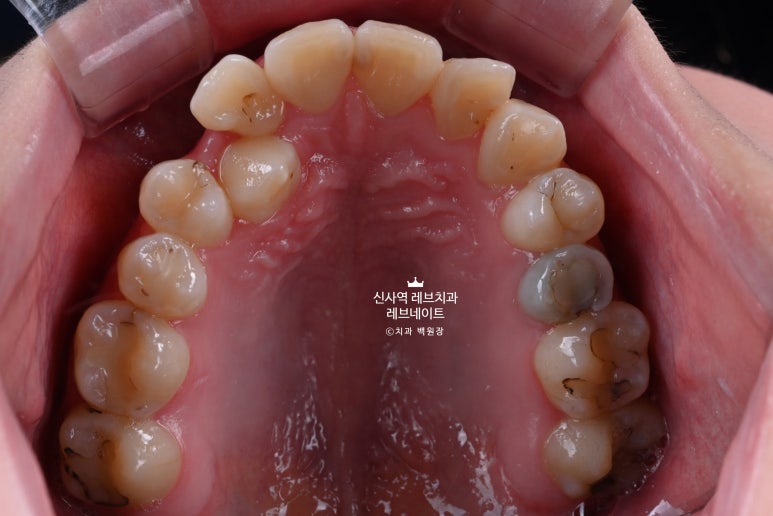

다시 한 번 자세히 보면, 치아 색이 꽤 얼룩덜룩해보이는 것을 아실 수 있을거에요.

사진을 찍어두고 4개를 신중하게 골라야만 했습니다......

그래도 가운데 앞니는 배열이 고르고, 모양도 괜찮은 편이었기에

위에 표시해 둔 4개의 치아를 모양을 최대한 잡아서 한 번 예쁘게 연출을 해보기로 했습니다.

결국 대문니 두 개의 색깔과 질감에 맞추어 라미네이트를 해야하는 어려운 상황

사실 라미네이트를 할 때 여러개의 치아를 넉넉히 깎고 치료하면 아주 편합니다.

여러개를 치료해야, 공간의 배분도 쉽고 라미네이트의 색상도 통일하기 쉽거든요?

근데 인상에 가장 중요한 가운데 앞니 두개는 두고, 나머지 네개를 그것에 똑같이 맞추려고 보니

앞니의 자연스러운 질감과 저 알록달록한 색감을 재현할 수 있을까... 하는 생각이... 드는...

엄청난 과제를 만나버린 것이죠.